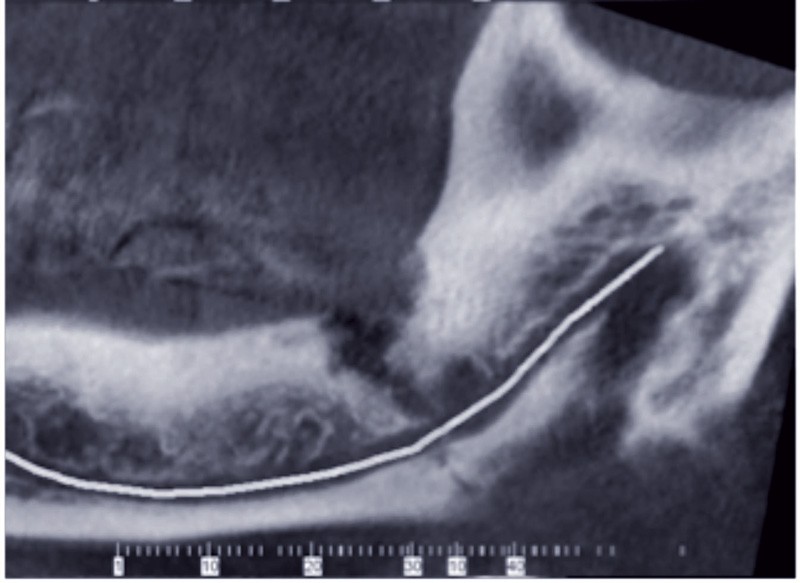

Les dents évoluées sur l’arcade présentent généralement peu de problèmes lors de l’extraction. Les difficultés rencontrées alors sont essentiellement en rapport avec l’anatomie radiculaire. En revanche, dès qu’il y a rétention, même partielle, la difficulté augmente et l’abord doit être différent. Anticiper le geste chirurgical dans ce cas est une préoccupation légitime pour l’odontologiste. Il doit savoir déterminer le degré de difficulté de cet acte et le rapporter à ses propres compétences, et envisager, le cas échéant, d’adresser le patient à un spécialiste. Tout patient saura gré à son praticien d’avoir su déléguer, mais lui tiendra grief d’avoir interrompu une extraction ou d’y avoir passé deux heures, sans tenir compte des suites opératoires pénibles : douleurs, trismus, hématome, etc.

L’évaluation du degré de difficulté d’extraction repose sur de nombreux paramètres, souvent interdépendants. Bien que largement cités dans la littérature, l’association de ces paramètres avec la difficulté d’extraire est parfois difficile à objectiver.

Un premier essai visant à déterminer ces critères a été proposé par Mac Gregor en 1976 [1]. Les variables proposées, uniquement basées sur l’étude radiographique (panoramique) sont significativement associées à une augmentation du temps passé par le chirurgien à extraire la dent. Ils comprennent la position de la dent de sagesse dans l’os (verticale, mésio/disto angulée, horizontale), l’angulation de la deuxième molaire, la hauteur de l’os mandibulaire, la forme et nombre des racines ainsi…